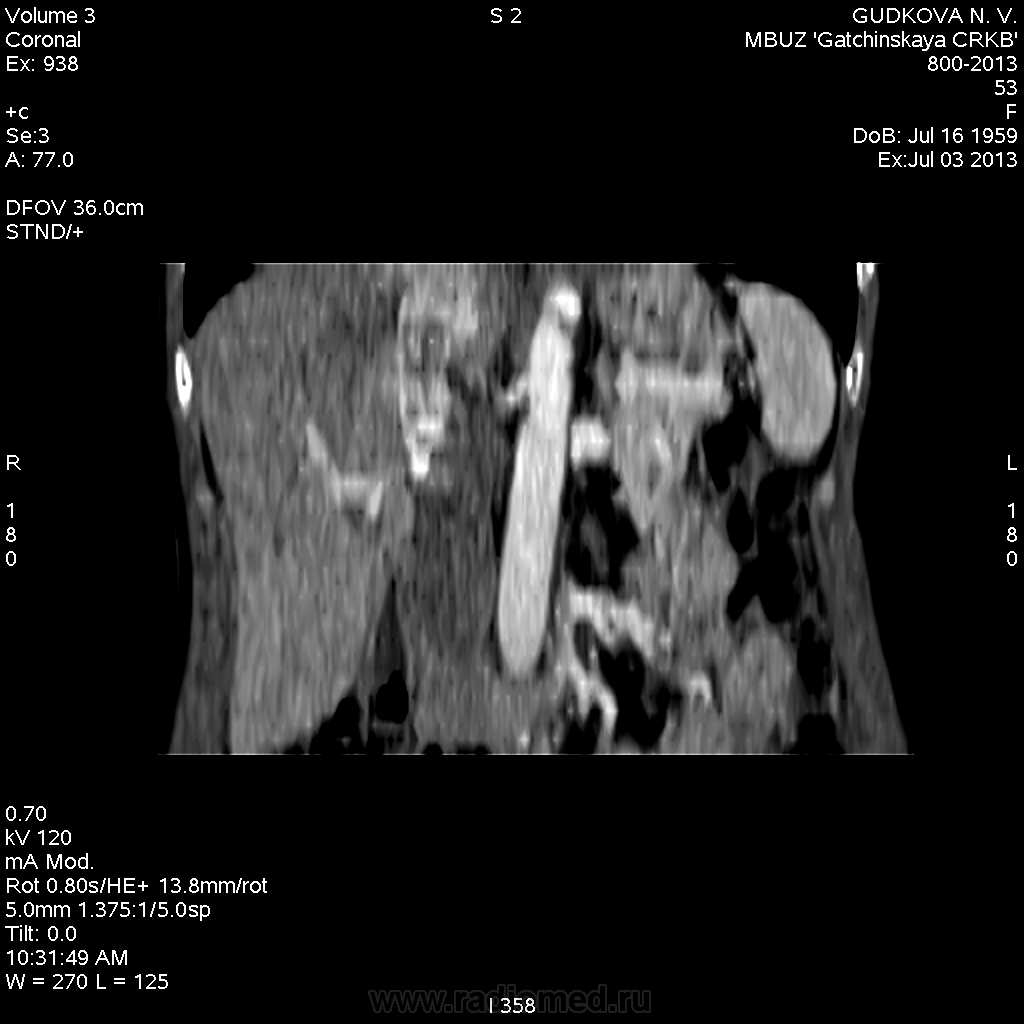

В артериальную фазу - интенсивное накопление контраста, как раз в области этого расширения, в 4-5 сегментах печени.Выше и ниже - идет неизмененная НПВ, без контраста (фаза артериальная!) В венозную фазу - небольшая гиперденсная зона перикавально в печени - и все.

На 3d-реконструкциях выглядит как кавернозная гемангиома, по форме напоминающая желчный пузырь (который я, кстати, не вижу, а УЗИсты описывают) Если это - ж.п., почему так интенсивно копит контраст, и вообще, расположение такое нетипичное?

Образование печени ли это вообще? Не перикавальное внепеченочное нечто? (и что?)

Это нижняя полая. Заброс контраста в нижнюю полую вену и контрастирование веточек портальной вены в артериальную фазу бывает при неправильной технике проведения болюса. Посмотрите тут: http://www.radiographia.ru/sites/default/files/abdominal_ct_protocols.pdf

Заброс контраста в нижнюю полую в артериальную фазу может быть при пассивном венозном застое, как следствие перикардита или сердечной недостаточности.у меня один раз тоже такое было, голову сломала, но в Прокопе все же нашла.

Да, это нижняя полая вена.

Мелкую кисту в правой доле печени (S6) я нашел. Ее нет на представленных сканах(выложил то, что меня смутило), но, думаю, именно ее описывают УЗИсты. И размеры совпадают, и гипоэхогенность характерна для кисты.